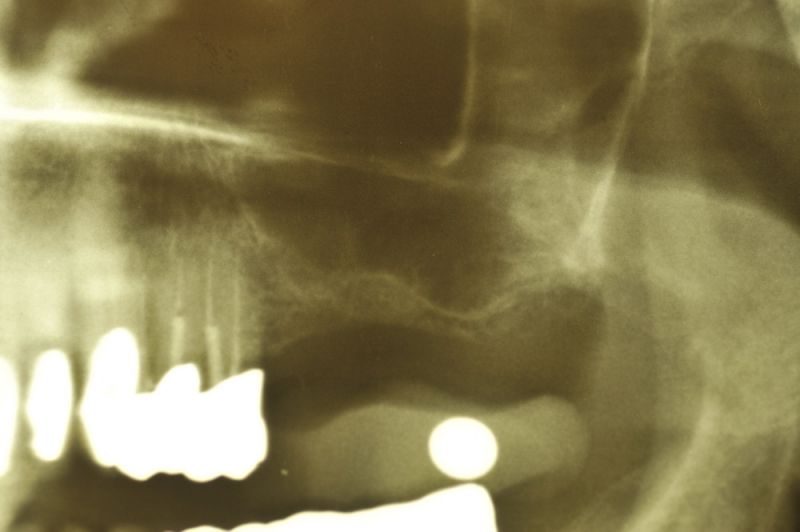

So sehen Granulome aus, die sich an und um die Wurzelspitzen chronisch beherdeter Zähne gebildet haben.

In aller Regel sind diese Zähne sehr lange Zeit vollkommen beschwerdefrei und erst im Rahmen röntgenologischer Untersuchungen werden derartige Befunde offenbar.